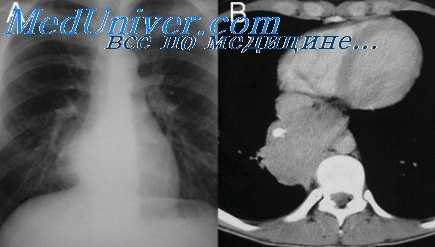

Сравнительно нередко в этих случаях после струмэктомии, произведенной на шее, возникает «медиастинальный рецидив». 7% медиастинальных струм злокачественны (Merlier, Eschapasse, 1973). Малигнизация не имеет внешних характерных проявлений. Сильное сдавливание окружающих органов (например, полой вены) не является типичным, оно может быть вызвано и доброкачественной опухолью. Крупная доброкачественная опухоль средостения, подтвержденная гистологически, включившись в верхнюю апертуру грудной клетки, вызывает сдавливание ветвей верхней полой вены и значительное повышение венозного давления. Расширенные вены создают характерную коллатеральную сеть. При ангиографии полой вены эта коллатеральная сеть отчетливо видна.